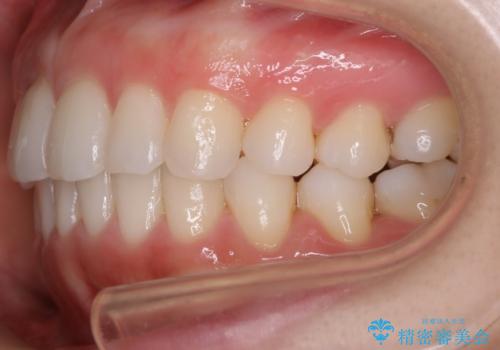

【非抜歯】前歯のガタつき マウスピースの部分矯正

- 上下の前歯の細かいガタつきの治療をご希望されて来院されました。

奥歯部分にはガタつきや噛み合わせの問題などがほとんど見られず、前歯のガタつきも軽度だったため、インビザライン ライト パッケージでの部分矯正を行うこととなりました。

今回のケースでは奥歯の噛み合わせに問題がほぼみられなかったため、前歯の位置のみに焦点を当て部分矯正を行いました。

適応されるケースが限られるものの、適応であった場合の治療期間は全体矯正と比べると格段に短くなり、費用も抑えられます。